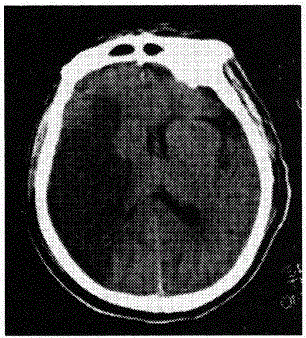

患者,男性,60岁。清晨睡醒后左侧肢体无力,刷牙时无法拿杯,有糖尿病和高血压病史无心脏病史,半天后急诊。查体:左侧肢体肌力3级,腱反射高于右侧,左侧Babinski征阳性。左侧肢体痛温觉减退。脑CT见图示:可能的诊断为

本题考查目的是综合临床资料和CT图像作出脑血管的诊断。从上题的脑缺血性卒中与脑出血性卒中的鉴别要点表中很容易得出标准答案D脑血栓形成。短暂性脑缺血发作的体征一般1~2小时恢复,而且以单肢瘫等局限体征为多见。CT图像上一般没有梗死灶。脑栓塞一般在活动状态下,数秒钟即出现明显脑症状,大多数患者有房颤等栓塞灶的来源。这些均与本例不符合,故缺血后卒中以脑血栓形成为正确答案。